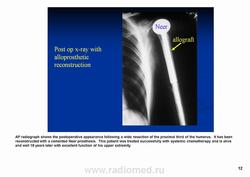

Лечение. Как при обычной остеосаркоме.

Исход как и при обычной остеосаркоме, неблагоприятный.